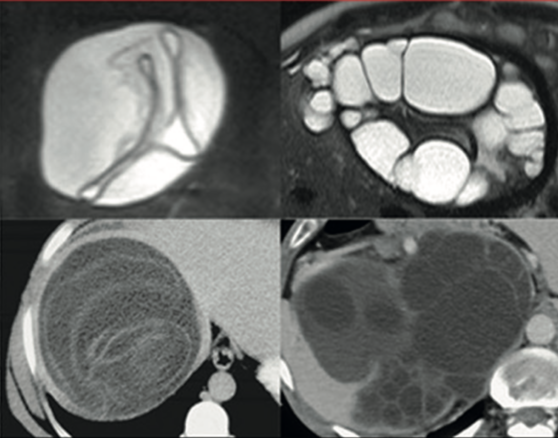

El enfoque de observar y esperar (WW), consiste en un seguimiento ecográfico regular sin intervenciones sobre el quiste, en ausencia de reactivación o complicaciones. En la mayoría de los centros con alto número de pacientes tratados, este abordaje es actualmente el de elección para los quistes CE4 y CE5 inactivos no complicados. El enfoque de ubicar la Equinococosis Quística (EC) en una etapa específica de la clasificación ultrasonográfica (US), postura defendida por los expertos de la OMS-IWGE, tiene como objetivo optimizar el tratamiento de los pacientes con equinococosis quística, evitando el sobretratamiento, su impacto en la vida diaria y los costos asociados1.

En este contexto, el enfoque de observación y espera, para los quistes CE4 y CE5 asintomáticos y sin complicaciones, es seguro y está respaldado por una evidencia cada vez mayor. Sin embargo, este enfoque todavía está poco adoptado y por lo tanto, el inadecuado tratamiento de los quistes inactivos sigue ocurriendo, lo que expone a los pacientes a riesgos innecesarios derivados del sobretratamiento y a altos costos al sistema público de salud.